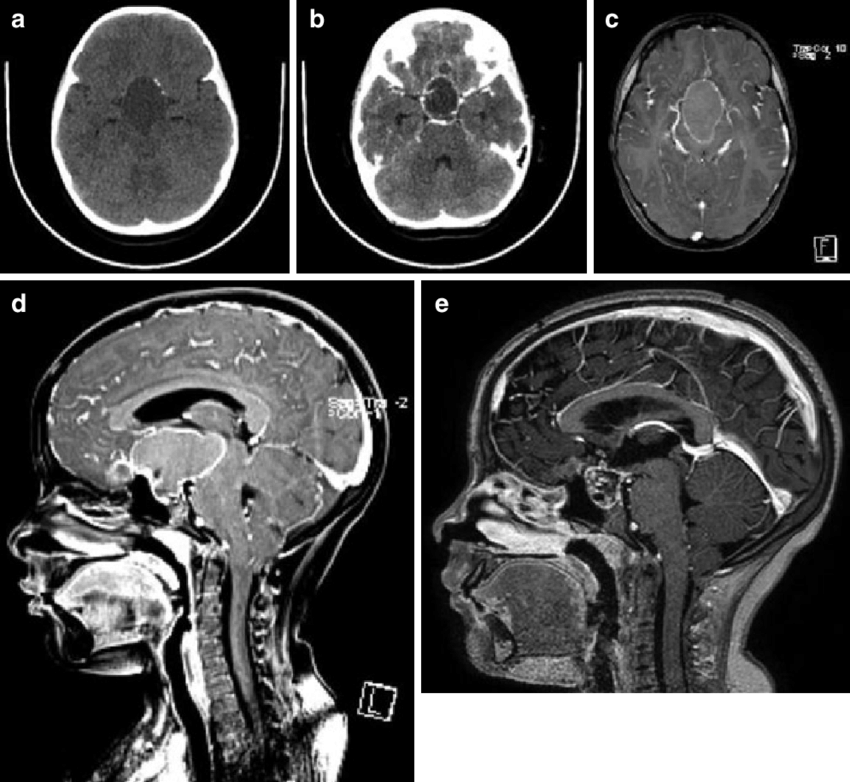

INC旗下国际神经外科顾问团(WANG)专家成员James T. Rutka教授在论文中表示:了解鞍区和鞍上区解剖是选择颅咽管瘤较好手术入路的关键...

颅内颈动脉位于视神经的外侧。颈动脉常突出于蝶窦外侧壁,视神经管突出于蝶窦上外侧,三叉神经二分支突出于蝶窦下外侧。视神经、动眼神经、颈动脉...

颅咽管瘤是一种来源于胚胎残余组织的良性肿瘤,颅咽管瘤约占儿童全部脑瘤的6%。任何年龄的人都有可能被诊断为颅咽管瘤,但在5到14岁之间较容易被诊...

颅咽管瘤 是起源于神经上皮的肿瘤,由鳞状细胞沿原颅咽管道长出。它们的发病率在每10万人年0.5至2.5之间,不因性别或种族而有所不同。颅咽管瘤占全部...

儿童颅咽管瘤是一种少见的、鞍区或鞍旁区胚胎性畸形的低级别组织学恶性肿瘤。由于颅咽管瘤与视交叉、脑垂体和下丘脑在解剖学上的邻近关系,其不良...

儿童期颅咽管瘤 是少见的,蝶鞍或鞍旁区域的胚胎发生畸形,伴有低度组织学恶性肿瘤。颅咽管瘤由于接近视交叉,脑垂体,经常影响儿童的生活质量(...

颅咽管瘤是由鞍区或鞍上区Rathke囊的残余细胞形成的肿瘤,具有囊性和实型成分。虽然它们是良性的,WHO为I级,但由于该病难以治愈,使得它们的生长行为...